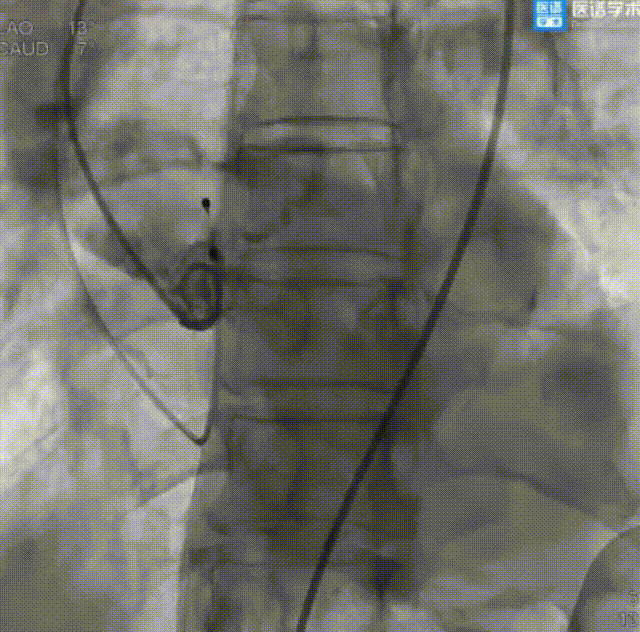

导丝成功跨瓣

VitaFlow生物瓣膜成功释放

VitaFlow生物瓣膜植入后即刻造影

球囊后扩

球囊后扩后造影

成功回撤二尖瓣球囊系统和导引鞘后,继续行经股动脉主动脉瓣置换术。术中顺利送入导丝建立入路,导丝成功跨瓣后送入22 mm球囊至主动脉瓣预扩张,后送入TAV27 mm瓣膜至主动脉瓣处。在180 bpm快速起搏的同时释放瓣膜,即刻造影显示中度瓣周漏,遂又送入25 mm球囊至主动脉生物瓣膜处行后扩张,瓣周漏较先前明显减少。术后超声显示平均主动脉跨瓣压差为3 mmHg。